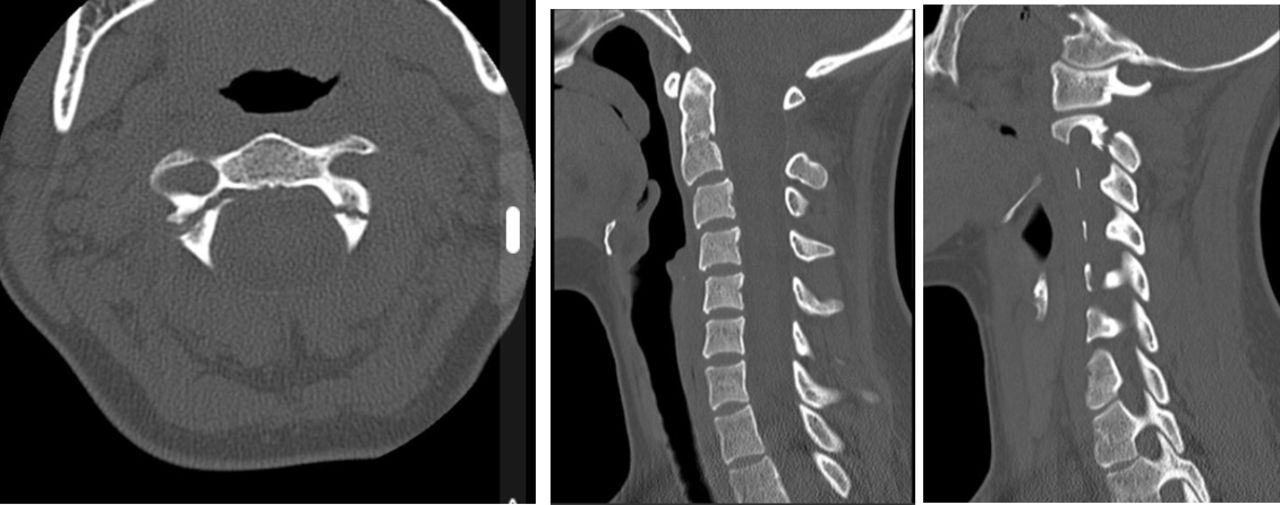

Hangmans Fracture

Hangman's fracture - Wikipedia Hangman's Fracture - Physiopedia Hangman's Fracture, C2 Fracture - Everything You Need To Know - Dr. Nabil Ebraheim - YouTube Hangman fracture | Radiology Reference Article | Radiopaedia.org | Hangmans Fracture